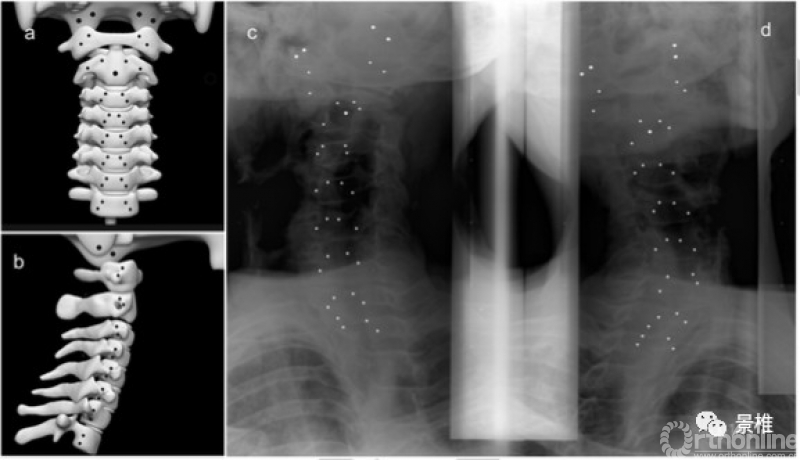

把钽珠和铅珠植入5具冰鲜标本的颈椎椎体,套上各类制动支具,标本头部进行屈伸、旋转、侧屈活动,X线透视观察颈椎活动受限率(MRP)。

■●▲▬*分别是5具标本

halo架对颈部制动效果最好,能减少70%的屈伸、77%的侧屈、92%的旋转。

硬颈围最不行,只能减少41%的屈伸、29%的侧屈、64%的旋转。

制动效果:硬颈围<SOMI<脊柱平板<halo架。